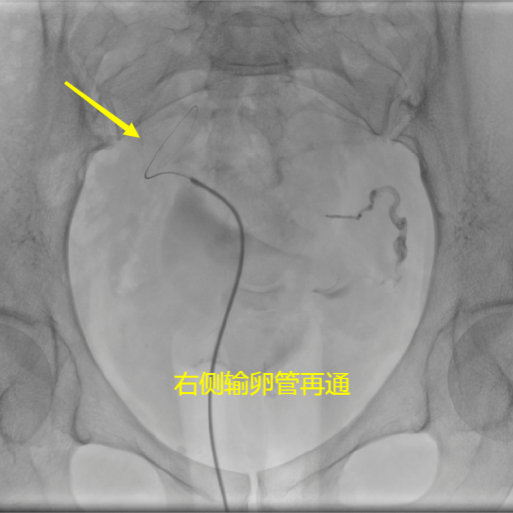

輸卵管造影後(hòu),發(fā)現輸卵管近端阻塞,輕度阻塞可通過(guò)造影劑直接進(jìn)行疏通,類似婦科輸卵管通水的作用:如阻塞嚴重,則可行輸卵管介入再通術。即在X線引導下,將(jiāng)微導絲、微導管通過(guò)陰道(dào)→子宮→輸卵管自然管道(dào),采用導管導絲技術疏通輸卵管,再沿微導管注射藥物,以達到疏通輸卵管、消除輸卵管傘端炎症、防止輸卵管再黏連的目的。

國(guó)内外文獻報道(dào),總體輸卵管再通率約爲90%。